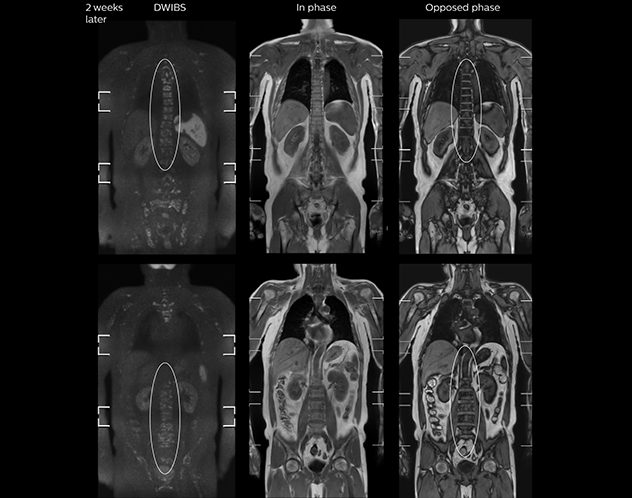

Coronal DWIBS is faster and improves image quality

“Switching to coronal DWIBS – rather than axial – further shortens scan time,” says Mr. Naka. “Important is that a dS SENSE factor of 5 shortens exam time while high image quality can be maintained, thanks to Ingenia’s dStream architecture.” He adds that the coronal orientation also avoids artifacts that are specific to combining axial images.

“When we use a coronal DWIBS acquisition, we can perform a full whole body examination, including other required sequences, within 30 minutes,” he says.

“This is considerably faster than the previously used exam with axial whole body DWI, which took more than 45 minutes,” he notes. “A shorter exam is more patient-friendly and allows us to also use it on patients in poor health who would have difficulty tolerating a long exam. Limiting the exam time is also helpful for scheduling, because it fits in a normal single exam timeslot.”

mDIXON FFE enriches the whole body exam without scan time penalty

Kawasaki Sawai Hospital’s whole body protocol also includes an mDIXON FFE sequence. Because mDIXON provides images for four contrast types – water only, fat only, in-phase and out-of-phase – from a single acquisition, it is useful in many ways.

“mDIXON FFE allows us to quickly get information we need to assess the presence of fat. That gives us more information when we need to diagnose bone lesions, and when we are asked to judge fat-containing lesions such as hepatocellular or renal carcinoma,” Dr. Nobusawa says.

“The mDIXON fat images can help us to differentiate fatty bone marrow from bone lesions. This is especially useful in elderly people, who tend to have fattier bone marrow. The water images provide a high signal-to-noise ratio in the intestinal canal, which is valuable for visualizing lesions in the colon,” he says.

“In-phase and out-phase sagittal T1-weighted FFE images help us to visualize and further characterize bone lesions such as metastasis and bone-marrow hyperplasia that have high signal on DWI. These images are also used throughout radiotherapy, to monitor changes in the fatty bone marrow.”